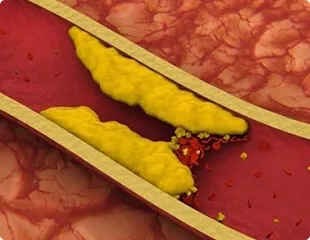

उच्च रक्तचाप में संवहनी सफाई क्यों महत्वपूर्ण है

रक्त के थक्कों के कारण धमनियाँ बंद हो सकती हैं और यहाँ तक कि पूर्ण हृदय गति रुक भी सकती है।

कोलेस्ट्रॉल प्लेक वाहिकाओं में खराब रक्त प्रवाह का कारण बनता है और रक्तचाप बढ़ाता है।

अवरुद्ध रक्त वाहिकाएं भंगुर हो जाती हैं, जिससे आँतरिक अंगों का विघटन होता है।

Cartiofin कार्डियोवास्कुलर सिस्टम को नियंत्रित करने और रक्त वाहिकाओं को मजबूत करने में मदद करता है।

धमनी (Arterial) की जटिल संरचना कोलेस्ट्रॉल प्लेक की दीवारों को मजबूत करने और उनकी लोच को बहाल करने में मदद करती है।

रक्त वाहिकाओं को साफ करने के सामान्यीकरण में योगदान देता है।

Cartiofin उच्च रक्तचाप के कारणों को बेअसर करने में मदद करता है।